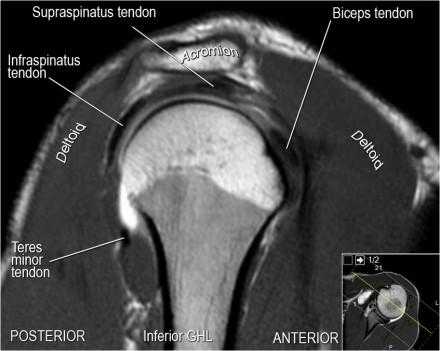

Нормальная корональная анатомия плечевого сустава и контрольный список

- обратите внимание на клюво-ключичную связку (coracoclavicular ligament) и короткую головку двуглавой мышцы (short head of the biceps).

- обратите внимание на клювоакромиальную связку (coracoacromial ligament).

- поищите импинджмент надостной мышцы за счет остеофитов в акромиально ключичном суставе или из-за утолщения клювовидноакромиальной связки.

- поищите скопление жидкости в подакромиальной сумке и повреждение сухожидия надостной мышцы

- поищите повреждение сухожилия подостной мышцы